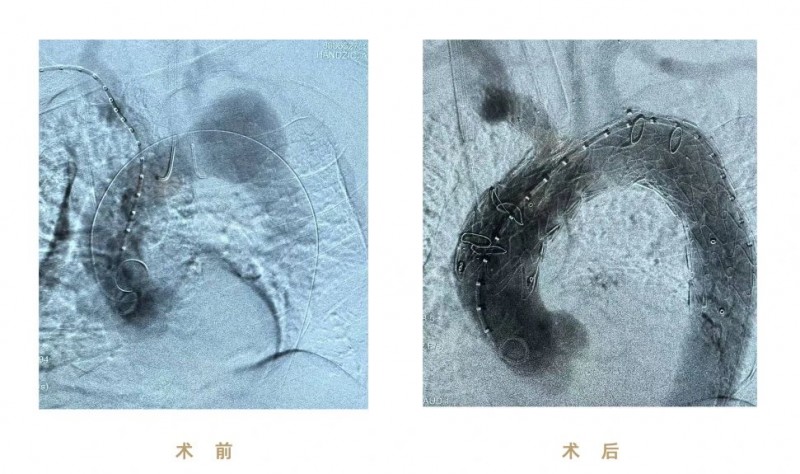

(圖:術(shù)前、術(shù)后影像)

本次手術(shù)使用先健CS一體式弓部三分支重建系統(tǒng)進(jìn)行腔內(nèi)修復(fù),逐次完成通路建立、CS主體支架植入及精準(zhǔn)釋放、弓上三分支(無(wú)名動(dòng)脈、左頸總動(dòng)脈、左鎖骨下動(dòng)脈)依次超選及分支支架植入,全程造影顯示支架形態(tài)良好、無(wú)移位及內(nèi)漏、三分支血流通暢,達(dá)到理想的隔絕與血供重建效果。